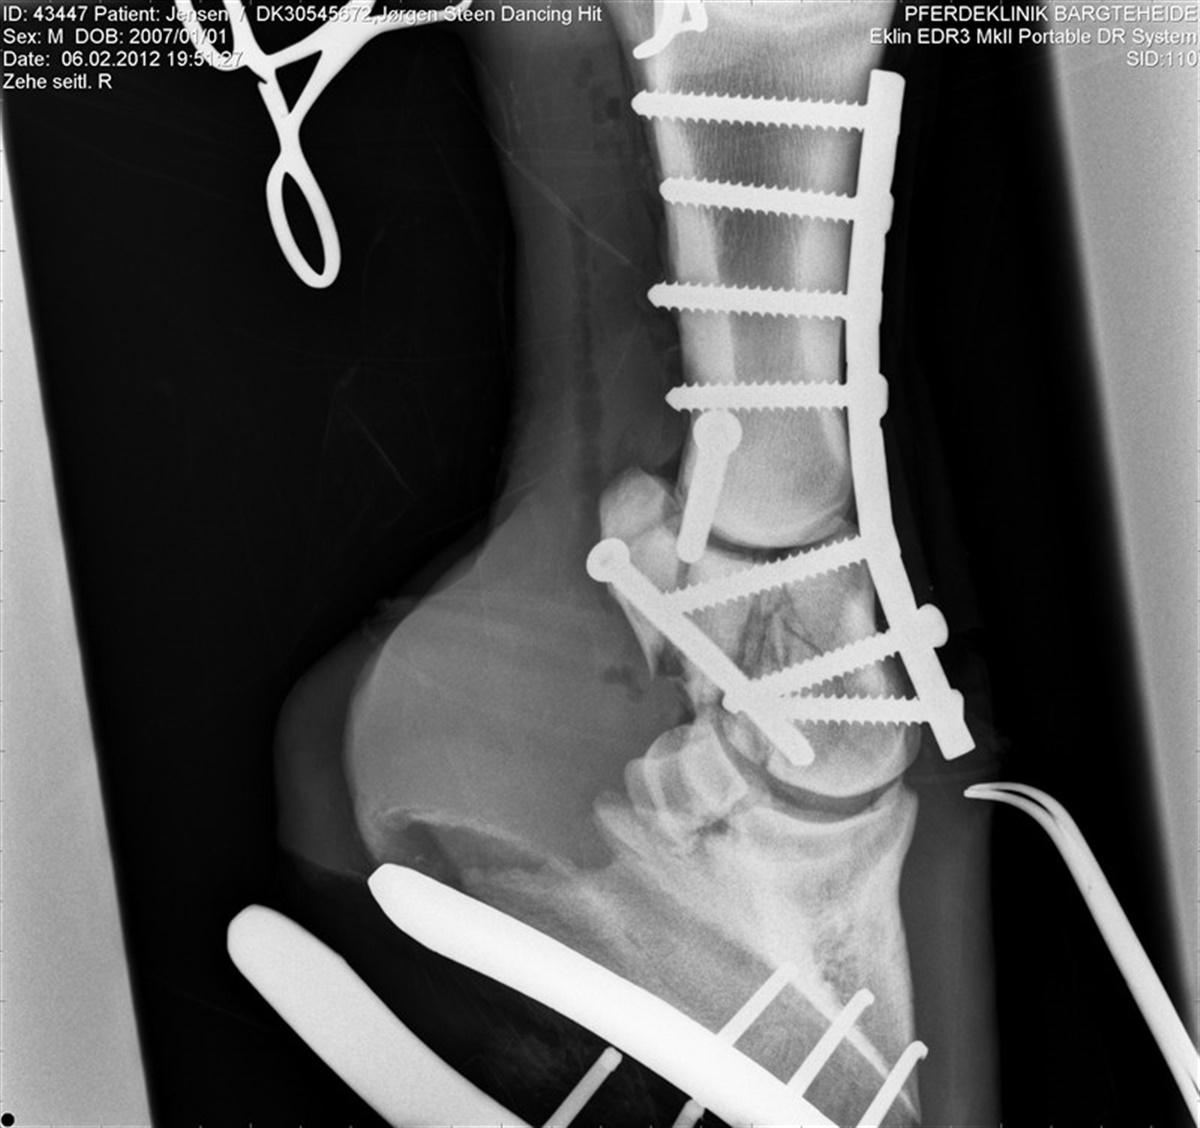

Den natsorte avlshingst ERA Dancing Hit brækkede mandag benet under longering i ridehallen. Under longeringen sprang hingsten op i luften af kådhed, men i landingen brækkede han benet. Hingsten blev beroliget og smertebehandlet og derefter kørt til operation i Nordtyskland hos dyrlæge Jahn. Her konstaterede man at hingsten havde flækket kronbenet i tre stykker. Under den efterfølgende operation blev benet sat sammen med otte skruer. Konsekvensen er, at hingsten aldrig får en karriere i sporten, men at hans gener forhåbentlig kan bevares for avlen, idet dyrlægen og hingsteholderen i fællesskab er enedes om at give hingsten en chance for at overleve skaden. Problemet er dog, at skaden kræver, at hingsten skal aflaste det skade ben og derfor skal han de næste seks uger aflastes i en sele, så han kun hviler med en fjerdedel af sin vægt på underlagt af hensyn til overbelastningsskader. Selen er konstrueret så hingsten kan bevæge sig frit rundt i boksen og også lægge sig ned. - Det er det værste jeg har været ude for i de 40 år med hingstestation, og at det så skulle ske for en hingst af den kvalitet, det er hårdt, siger Jørgen Steen Jensen. Jørgen Steen Jensen er naturligvis meget berørt af hændelsen, der på alle måder er et kæmpe tab. ERA Dancing Hit vandt dressurdisciplinen ved hingstenes materialprøve på Vilhelmsborg og hingstestationen skrev sig ind i historiebøgerne, da stationens springhingst Chandler samtidig tog sejren i springdisciplinen.